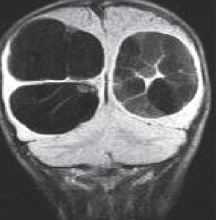

Кисты средней линии - киста прозрачной перегородки (cavum septi pellucidi), полость Верге (cavum Vergae) и киста промежуточного паруса (cavum veli interpositi) - являются нормальными структурами головного мозга плода. В течение 6 месяцев после рождения у большинства людей они запустевают, но могут и сохраниться, визуализируясь при этом на МРТ головного мозга. По-видимому, эти полости не имеют клинического значения и относятся к случайным находкам при томографии. Киста прозрачной перегородки (еще называют V желудочком) является медиальной стенкой боковых желудочков и ограничена спереди коленом мозолистого тела, сверху мозолистым телом и сзади столбами свода . Полость Верге представляет собой продолжение кисты прозрачной перегородки кзади и расположена между телами желудочков . Обычно обе кисты сочетаются. Киста промежуточного паруса расположена в крыше III желудочка (tela choroidea), между треугольниками боковых желудочков на уровне отверстий Монро. Она ограничена сверху мозолистым телом, cзади цистерной четверохолмия и снизу III желудочком.

МРТ головного мозга. Корональная Т1-взвешенная МРТ. Многокамерные эхинококковые кисты.